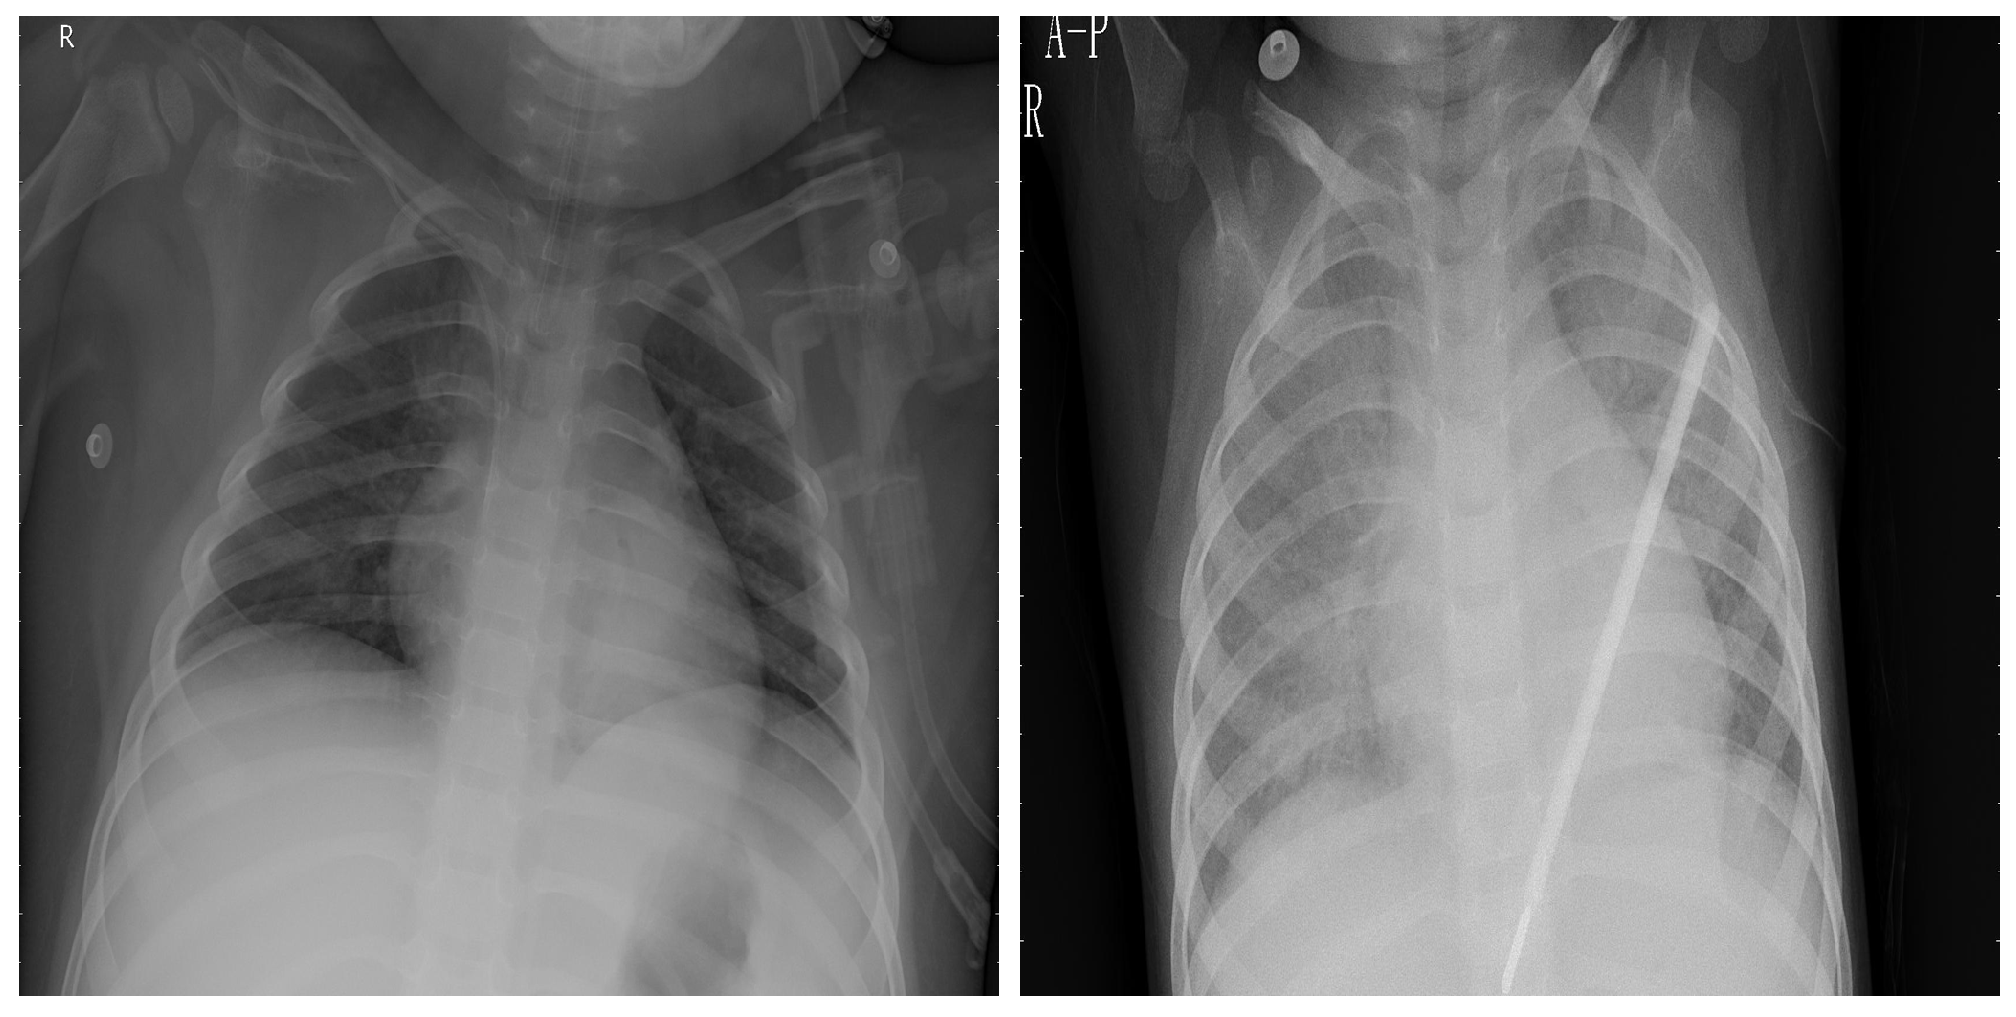

3.1. COVID-19 Image Data Collection (CIDC)

3.2. COVID-19 Radiography

3.3. BIMCV COVID19+

3.4. RSNA

3.5. Chest X-ray Images Pneumonia (CXRIP)